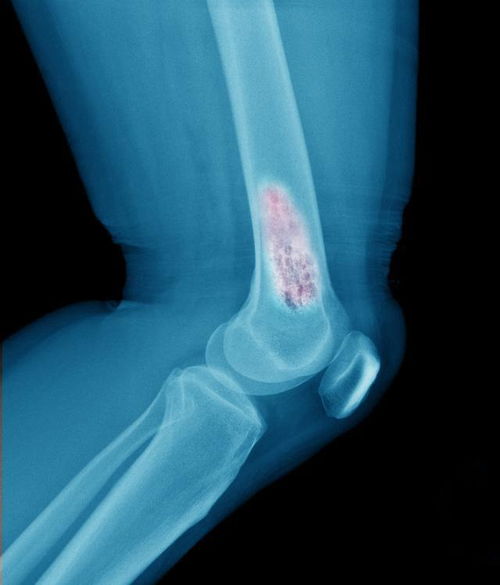

骨折是一种常见的外伤,特别是在年轻人当中。不幸的是,有时骨折会因为不当治疗而没有完全愈合。这就导致了另外一种状况,即需要挽回骨折的后果。在这篇文章中,我们将探讨几个可能干扰骨折治疗的误区,并讨论一些可以在治疗过程中采取的措施,以保证骨头可以完全愈合。

虽然很自然想要通过一些方法加快骨折的愈合,但有时这些尝试可能实际上会干扰愈合过程。以下是几个常见的骨折治疗误区:

冷敷和热敷是常见的止痛和预防肿胀的方法。然而,有时候这些方法会有相反的效果。冷敷会缩小血管,减缓血流,这使得机体增加微循环,而导致骨折处的血液供应减少。

骨折支架被用来稳定骨头并让它愈合。然而,如果支架没有正确使用,会导致如筋膜挛缩、关节僵硬等不良后果。如果支架过紧或过松,同样会导致不正常的压力分布,阻碍愈合。